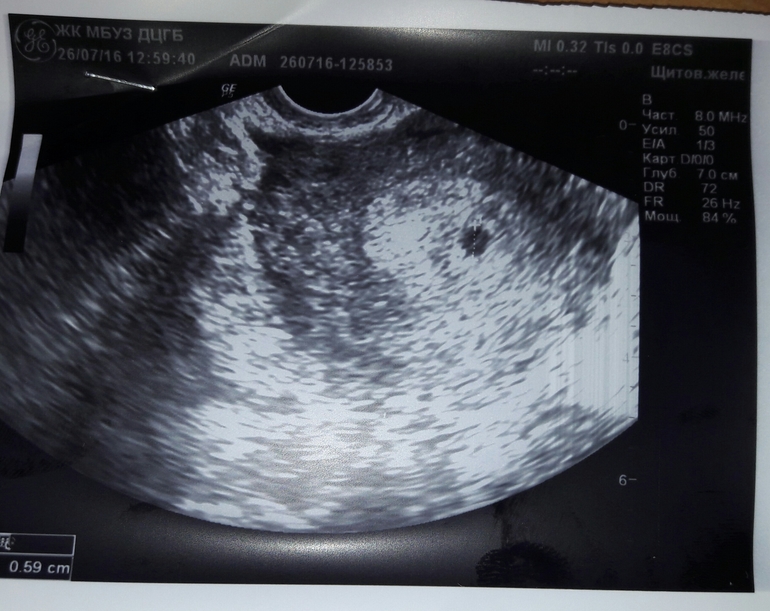

Сделала узи на 8 день задержки нашли плодное яйцо 3 мм соответствует 3 неделям.

Еще одно узи на 12 день задержки плодное яйцо 6 мм соответствует 3-4 неделям.